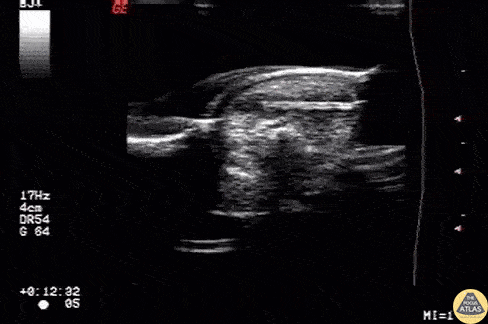

Wooden splinter located in the fingertip originally diagnosed as felon. Image courtesy of Robert Jones DO, FACEP @RJonesSonoEM Director, Emergency Ultrasound; MetroHealth Medical Center; Professor, Case Western Reserve Medical School, Cleveland, OH View his original post here